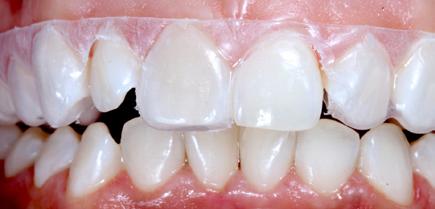

Restoring incisal wear and closing diastema with G-aenial A’CHORD. Courtesy of: Dr Aleksandra Slacan, Poland

Reshaping of teeth and diastema closure with G-aenial A’CHORD. Courtesy of: Dr Andres Silva, Spain